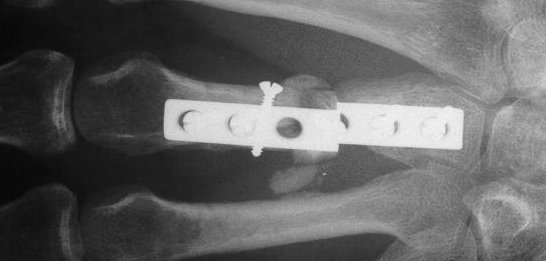

The treating surgeon debrided the wound and maintained length with intermetacarpal pins. When the wound was stable, the fracture was treated with bone graft, plate and screws.

He did well for three months, then broke his plate:

The plate was removed, and the fracture was replated, using more bone graft and larger screws. This plate  held for five months, then also broke. Additionally, a cross union to the ring metacarpal can be seen: